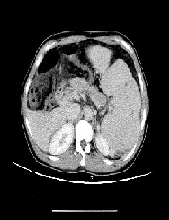

Leiomyosarcoma in A Patient with Accessory Kidney - Clinical Problems, Imaging and Treatment

Emil Enchev*, E. Dimitrov, G. Minkov, St. Nikolov, I. Ovcharov, Y. Yovchev